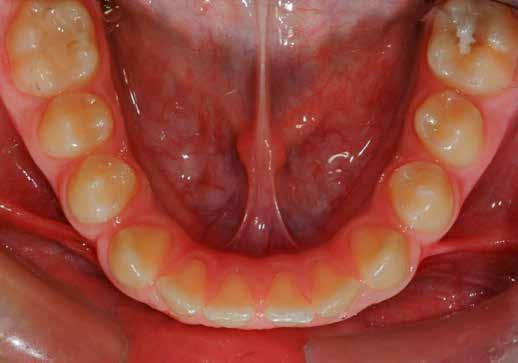

Lány páciensem I. fázisú kezelését 10 évesen kezdtük el bimaxilláris funkciós, kivehető készülékkel. Megfigyelhetőek a class 2-es eltérésnél tipikusan jellemző szűk felső és alsó fo-

gívek, valamint a nagy overjet, a mandibula disztál helyzete, továbbá a felső metszőfogak protrúziója, amelynek kialakulásához sokszor hozzájárul az ujjszopás is (1-3. képek)

A vegyes fogazati kezelési célok a fogívek tágítása és a mandibula meziális irányú növekedésének a biztosítása volt. Fontos, hogy az ilyen típusú készülékeket nem csak éjszaka, hanem napközben is – amennyit csak lehet – hordani kell a minél hatékonyabb működés érdekében. A 18 hónapos első fázisú kezelésnek köszönhetően az alap kezelési célok megvalósultak, sikerült a class 1-es okklúziót beállítani (4-7. képek).

Abban az esetben, amikor az első fázisú kezelési célok elérése megtörtént, de még nem törtek elő a maradó fogak az első moláristól az első molárisig – mintegy passzívan, csak éjszakánként hordva –, tovább folytatjuk a funkcionális kivehető készülék viselését.

Esetünkben 18 hónap után a maradó fogazat előtörése megtörtént, így rögtön folytathattuk a fogszabályozást.

A második fázisú kezelés Pitts-21-es fix fogszabályozó készülék alkalmazásával történt meg. A Pitts elveknek megfelelően a kezelési célok a felső középső metszőfogak megfelelő pozicionálása, a 12 fogas (6-ostól – 6-osig) mosoly, az ideális íves lefutású mosolyvonal kialakítása, továbbá az okklúzió finomítása voltak. Mint mindig, a felső fogíven mosolyvonal beállító esztétikai pozicionálást (Smile Arc Protection - SAP) alkalmaztunk, a mes-

terséges harapásemelés pedig az alsó hatosokra, majd később a felső négyesekre került (8. kép). Az intermaxilláris elasztikus gumihúzás class-2-ess vektorú volt annak érdekében, hogy a disztálharapás korrekciója tökéletes legyen (9. kép). A harapást beállító elasztikus gumihúzásokat – mint minden kezelésnél –, ebben az esetben is folyamatosan, az egész kezelés alatt 24 órában (étkezések kivételével) viselte páciensünk.

A második Pitts-21 fix készülékes fázis ideje 16 hónap volt (10-12. képek)

A fogszabályozás aktív fázisa után minden kezelésnél a retenció, a passzív helyben tartó fázis a kezelési eredmény megtartására rendkívül fontos!

Az Essix retainerek, az egy fogívre kiterjedő mélyhúzott sínek, valamint a felső és alsó frontfogakra orálisan ragasztott fix retainerek mellett, a harapás sagittális rögzítésében elengedhetetlen szerepe van az ún. Pitts Izom Tréning Splint-nek, amelybe a páciens élharapásban összeharap, így az megakadályozza az alsó fogsor visszamozdulását a disztálharapásos helyzetbe (13. kép)